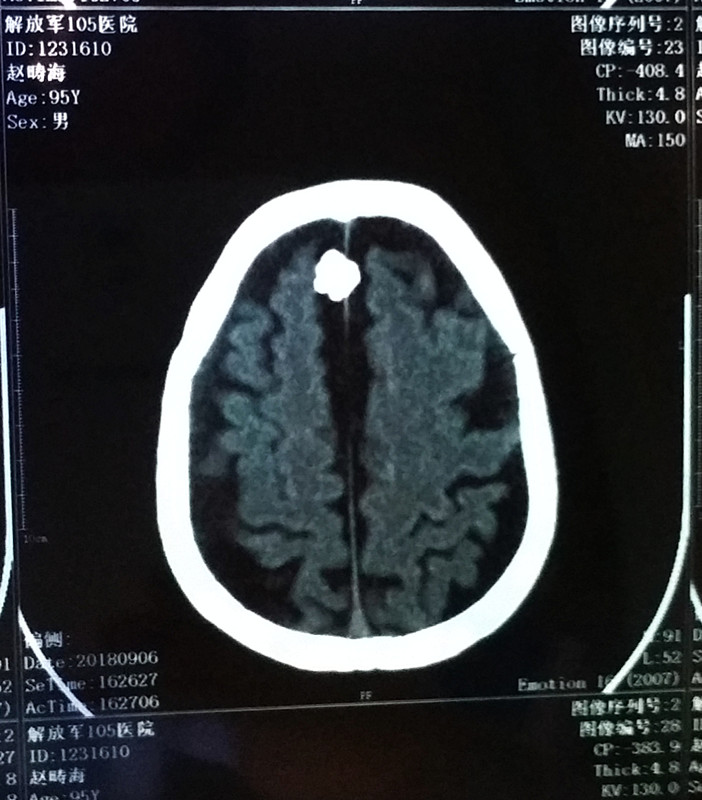

志愿军12军31师93团一营营长赵畴海

五次战役第二阶段,为接应91团后撤突围,奉命带领全营官兵阻击美军一个团时,被美军弹片击中,至今已经69年无法取出。

赵畴海原志愿军12军31师93团一营营长,今年已九十七岁高龄。参加了第五次战役、上甘岭战役和金城阻击战等。在第五次战役二阶段,为掩护91团和大部队后撤,奉命率领全营官兵阻击东援美军一个团,浴血奋战,顽强拼搏,不怕牺牲!在付出重大代价圆满完成任务后,面对险情,机智灵活,带领部队艰难后撤,保存了队伍,被誉为活着的‘’集结号‘’。